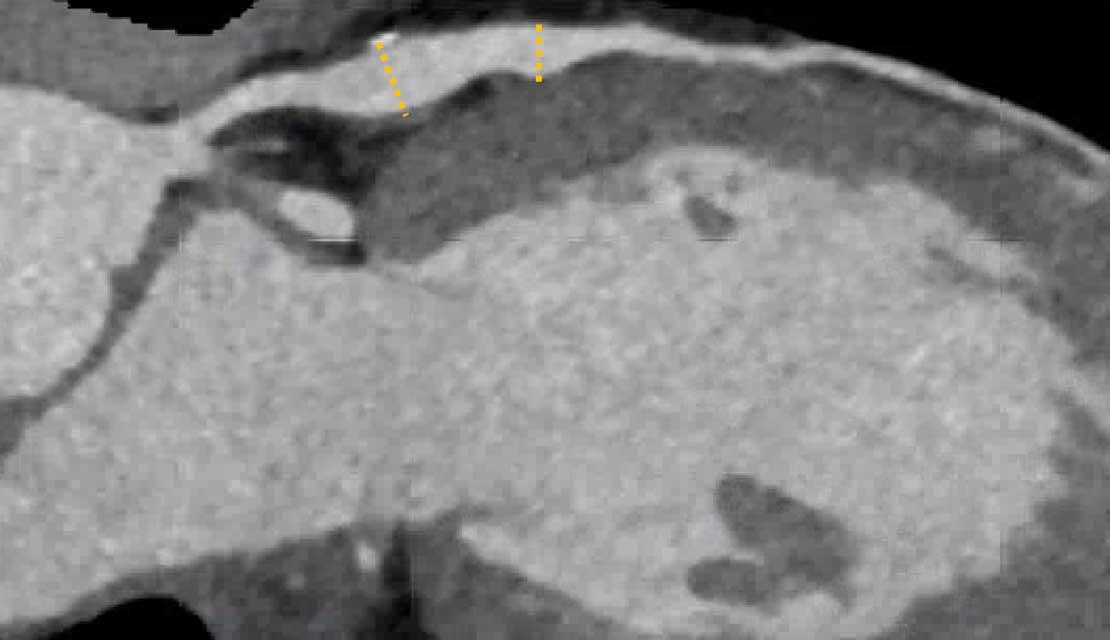

A: On the coronal image the so-called napkin-ring sign (dark area adjacent to the lumen, surrounded by a higher “ring-like” attenuation (white arrows). B: Tissue characterization on CT by HU number

Napkin-ring sign

The Napkin-ring sign is a qualitative high-risk plaque feature

on CTA (13).

It is defined as a central low-attenuation area adjacent to the coronary lumen

and a higher “ring-like” attenuation tissue surrounding this central area (14).

On histology, the area of low-attenuation corresponds to the necrotic core,

while the “ring-like” outer area correlates with fibrous plaque tissue.

The Napkin-ring sign is strongly associated with major adverse

cardiovascular events (15).